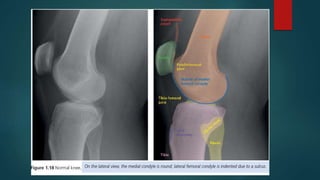

Skeletal X ray anatomy ,colour description, Imaging anatomy of musculoskeletal X rays, Diagnosis imaging anatomay, Radiology